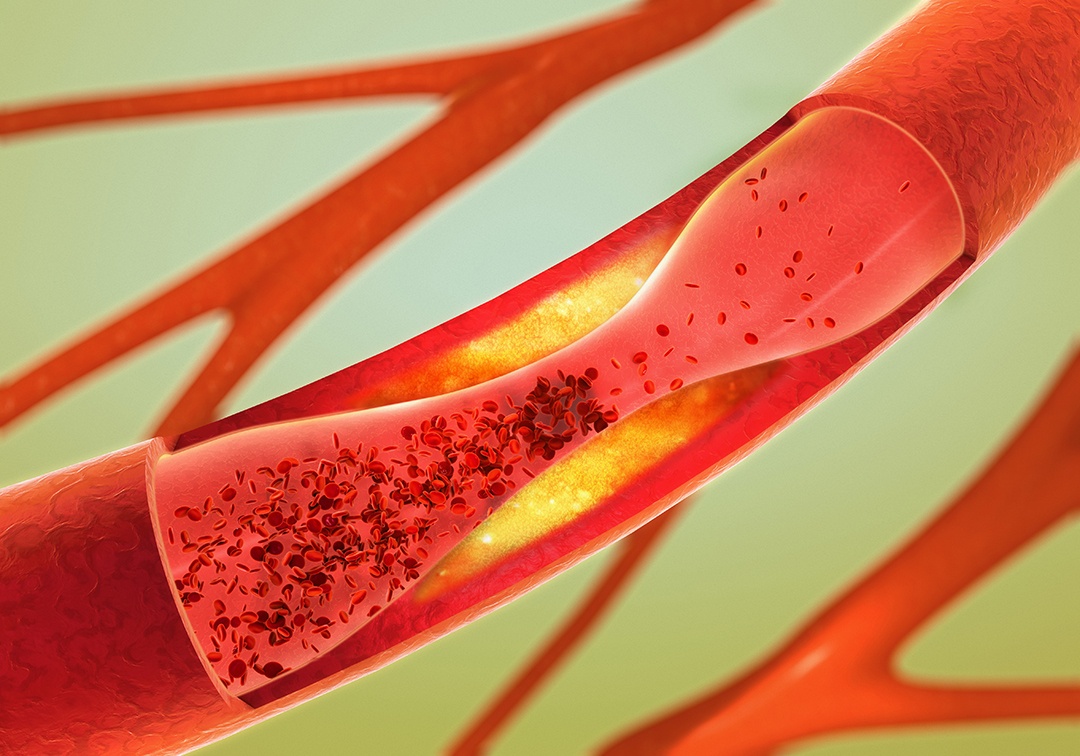

Chest pain (or angina) is a common complaint in the emergency room. Angina pectoris is a specific form of chest pain ...

More than 20% of stable outpatients with coronary artery disease (CAD) reported experiencing angina at least once per ...

New research presented at Transcatheter Cardiovascular Therapeutics (TCT) 2020 showed that while fractional flow reserve ...

Despite successful percutaneous coronary intervention (PCI), symptomatic patients without residual ischemia improved ...

Revascularization, a commonly used intervention for patients with stable ischemic heart disease, was not linked with a ...